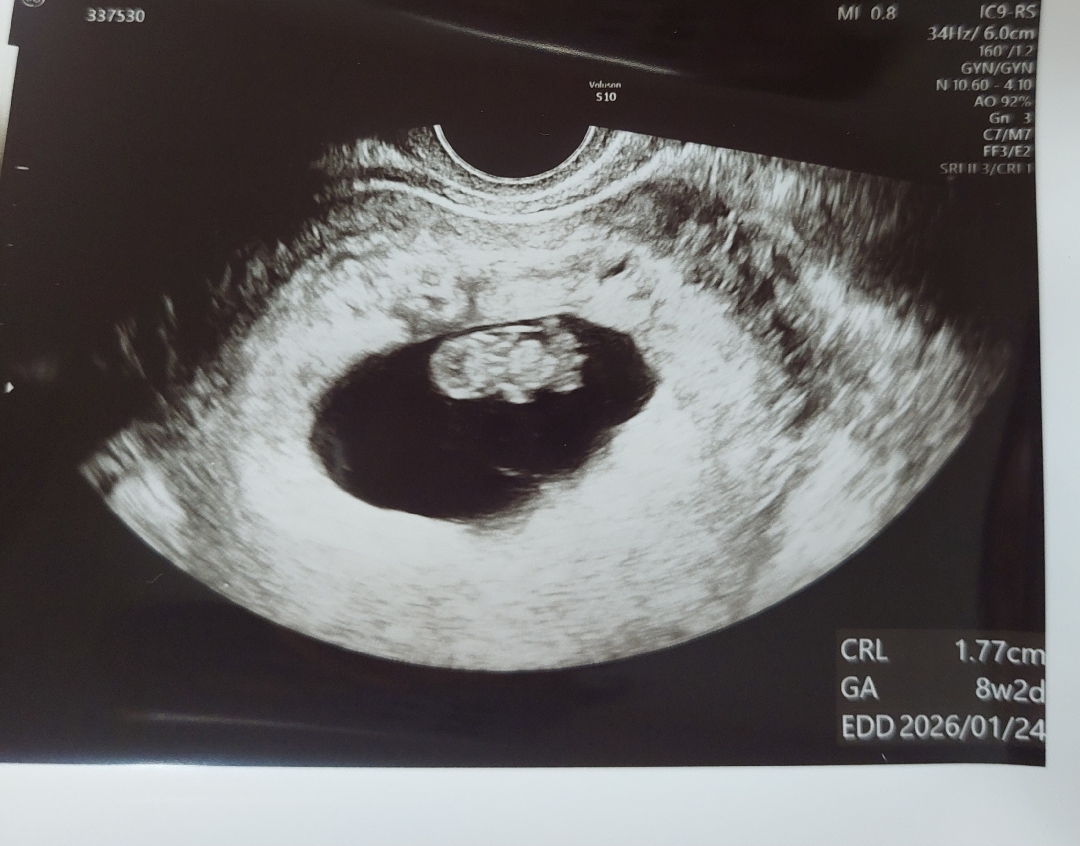

8주2일에 병원가구 이 다음 예약을 3주후로 잡아주셨어요ㅠㅠ 저번에 자라는속도가 늦더니 초기 계류유산을 한번 겪었어서 심장잘뛴다구들었는데도 불안하네요ㅠㅠ 2주마다 병원갔었는데...3주간 괜찮겠죠? 입덧도 어제까진 토하다가 오늘좀 괜찮은데...ㅠㅠㅠ